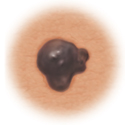

Asymmetry

When half of the mole does not match the other half

Border

When the borders (edges) of the mole are ragged or irregular